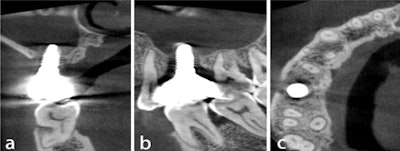

A week later, the patient reported having a headache and a runny nose, and there was still pus in his mouth. He underwent a panoramic x-ray, which revealed a foreign body in the sinus that ended up being another dental implant. After using imaging to localize the second implant, it was surgically removed. Also, the patient underwent a sinus lift, they wrote.

Figure 3: (a) Panoramic slice view after removal of the visible implant in the mouth

showing the presence of another implant in the maxillary sinus.